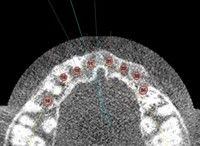

De acum si romanii pot beneficia de implantul dentar High Tech, o combinatie a metodelor inovatoare de reconstructie maxilo-faciala computerizata, prin metoda 3DDX Connect.Metoda de proiectie 3DDX Connect, introdusa pe piata din Statele Unite in ultimii 5 ani, reprezinta cea mai sigura tehnica de proiectare a implantului dentar, care astfel se va mula perfect structurii maxilo-faciale a pacientului, sustin specialistii. Metoda presupune prelucrarea datelor obtinute in urma unei tomografii, rezultatul fiind o proiectie 3D a mandibulei pacientului, care poate releva probleme sau detalii, alfel foarte greu de vazut. Astfel, medicul stomatolog are posibilitatea unei diagnosticari complete, reducand timpul alocat tratamentului si eliminand riscul de complicatii.

"Inserarea implanturilor dentare in pozitia optima, pentru a satisface cerintele estetice fara a neglija situatia anatomica de cele mai multe ori nefavorabila, poate constitui o problema chiar ti pentru cel mai experimentat chirurg. Reabilitarea orala complexa cu ajutorul unui numar mare de implanturi dentare inserate intr-o singura tedinta, necesita o planificare riguroasa. tablonul chirurgical este un ajutor infailibil in cursul unei asemenea proceduri. Cu ajutorul lui implantele se plaseaza in pozitia ideala, pentru maxim de comfort si estetica. Stresul operator este minim, timpul interventiei chirurgicale fiind mai scurt,